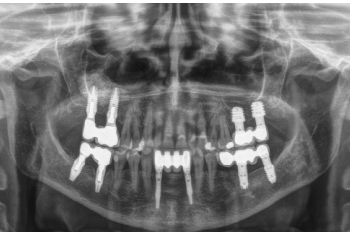

Presentamos el caso de una paciente femenina de 58 años que acude a la consulta dental para valoración de los molares 16 y 17 por dolor y movilidad. En la exploración clínica se observa movilidad de ambos y supuración a nivel del surco. La radiografía confirma nuestro diagnóstico encontrándonos con una pérdida ósea considerable y una perforación sinusal a nivel del ápice de ambos molares (Figura 2).

En el año 2007, con los implantes cortos sin pleno desarrollo y sin estudios que demostraran la importancia del diámetro frente a la longitud del implante el protocolo terapéutico para estos casos era muy diferente (Figuras 5-7), centrándose los esfuerzos en la búsqueda de un anclaje por longitud del implante en lugar de buscar la estabilidad bicortical (vestibular-lingual) que realizan los implantes cortos y anchos. Durante este tiempo se produce también

Una vez transcurridos seis meses tras la colocación de los implantes, se procede a la confección de la prótesis definitiva, en este caso mediante un puente cementado. Este protocolo protésico tampoco es el que seguimos actualmente donde prima la estanqueidad, el hermetismo y el empleo de prótesis atornilladas mediante elemento intermedio o transepitelial, pero en ese momento con este tipo de rehabilitaciones y la conformación de un perfil de emergencia “bio” en los pilares era como se terminaban estos casos (Figura 8)13-18. La implementación de los transepiteliales en las prótesis atornilladas abre un nuevo horizonte en la prótesis, cambiando el protocolo de nuestro grupo de trabajo hacia una mejora del sellado implante-prótesis, al mismo tiempo que se reducen los desajustes protésicos (al ser tomada la impresión directamente sobre el transepitelial y no a la conexión del implante) y se mejora la estanqueidad, disminuyendo entre otras cosas, el riesgo de periimplantitis19-20.

Finalmente, podemos observar la estabilidad de ambos tratamientos en la radiografía final a los 8 años, donde ambos se mantienen estables sin pérdidas óseas (Figura 13)